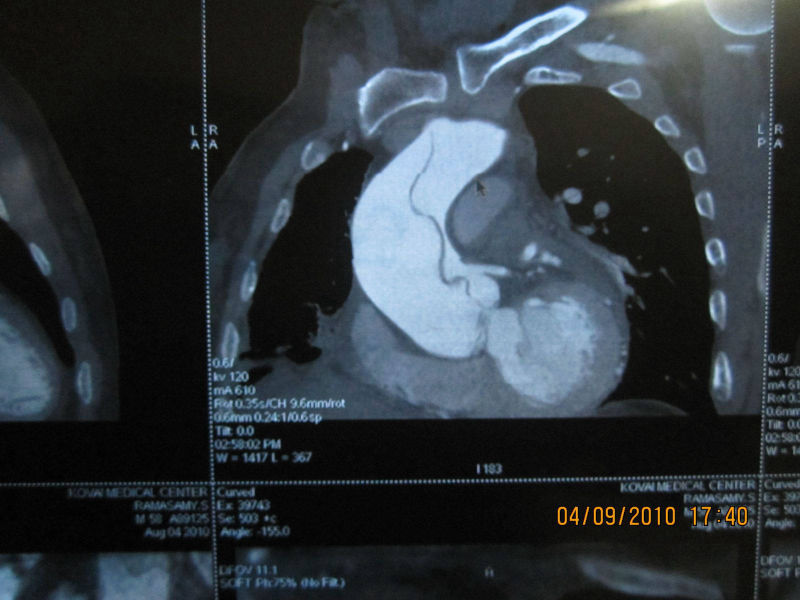

A 58 year old patient who had renal transplant 25 years earlier developed Aortic Dissection and Coronary Artery disease. He underwent successful Bentall's operation (replacement of aortic valve and ascending aorta and reimplantation of coronary arteries) with CABG (3 grafts). He did not require renal dialysis throughout his stay in the hospital and was discharged with normal renal function.